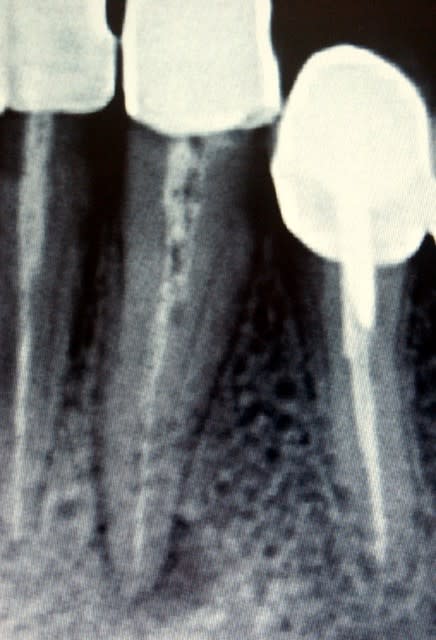

Ci-joint des radios d'une 12 qui présente d'abord un indice 1 puis qui est passé en indice 2 en l'espace de 2 mois. Je vous rassure, je n'avais pas fait le traitement initial (pas si horrible que ça), ni le compo. J'ai donc opté à l'époque pour le retraitement.

suite de la démo avec le passage d'une lésion que l'on pourrait qualifier de 4 (voire 3 si on compare avec ce que nous donne comme exemple les auteurs dans leur article) sur la radio initiale en une lésion de type 2 (en cours de cicatrisation) 3 mois après le retraitement.